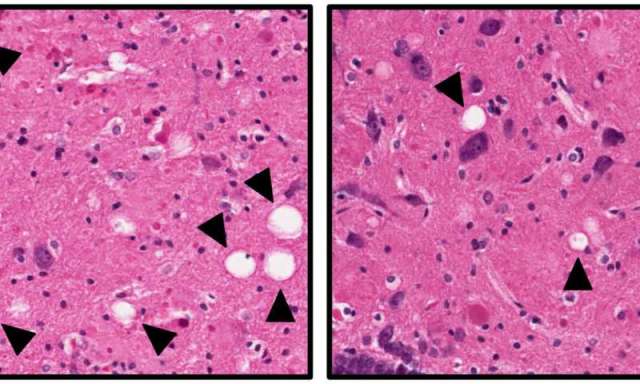

The image shows brain tissue from Alzheimer’s rats that were untreated (left) or treated (right) with the neuroprotective compound. The white “holes” indicated by the arrows are areas of brain cell death, and are more numerous in the untreated rats. Although the treatment protects the animals from neuronal cell death and Alzheimer’s-type symptoms, it does not alter the buildup of amyloid plaques and neurofibrillary tangles in the rat brains. The research from the Iowa Neuroscience Institute at the University of Iowa was published online in the journal Biological Psychiatry. Credit: Pieper Lab, University of Iowa.

The team also examined the brains of the rats at the two time points. They found that the traditional hallmarks of Alzheimer’s disease, amyloid plaques, tau tangles, and neuroinflammation, were dramatically increased in the Alzheimer’s rats regardless of whether they were treated with P7C3 or not. However, significantly more neurons survived in the brains of Alzheimer’s rats that had received the P7C3 treatment.